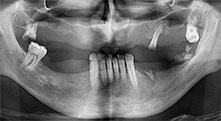

dentatura residua

Un paziente di 40 anni con una dentatura residua limitata desiderava un restauro basato su impianto. Dal momento che è un fumatore, era controindicato un rialzo del seno mascellare con una protesi fissa. È stata quindi programmata una protesi a barre.

Piezomed B6

La cresta alveolare è stata incisa su entrambi i lati tramite piezochirurgia (strumento utilizzato: Piezomed B6). Gli impianti sono stati posizionati con la stessa procedura e l'osso peri-implantare è stato costruito con la tecnica GBR.

impianti

I quattro impianti sono fissati come programmato. I molari mascellari distali possono comunque essere utilizzati per fissare la protesi in linea introdotta un mese dopo l'impianto.